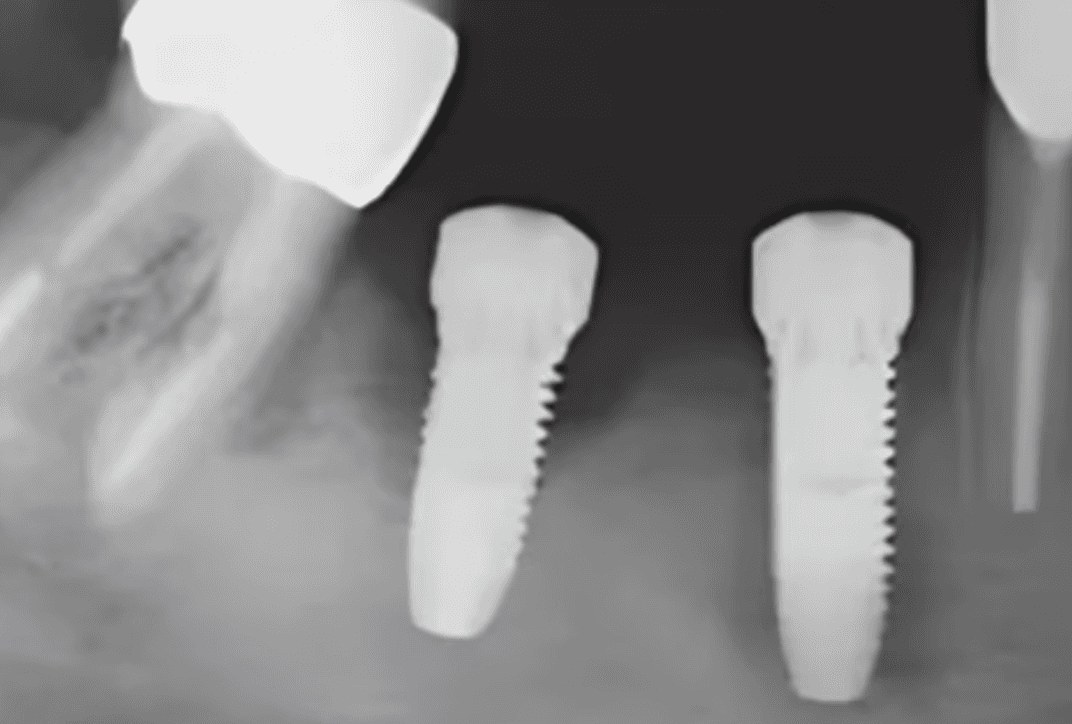

5. Verify Placement

Check that the cover screw sits flush with the implant platform and does not impinge on soft tissue. Radiographs can be useful for confirming proper seating, especially in critical cases or when learning the technique.